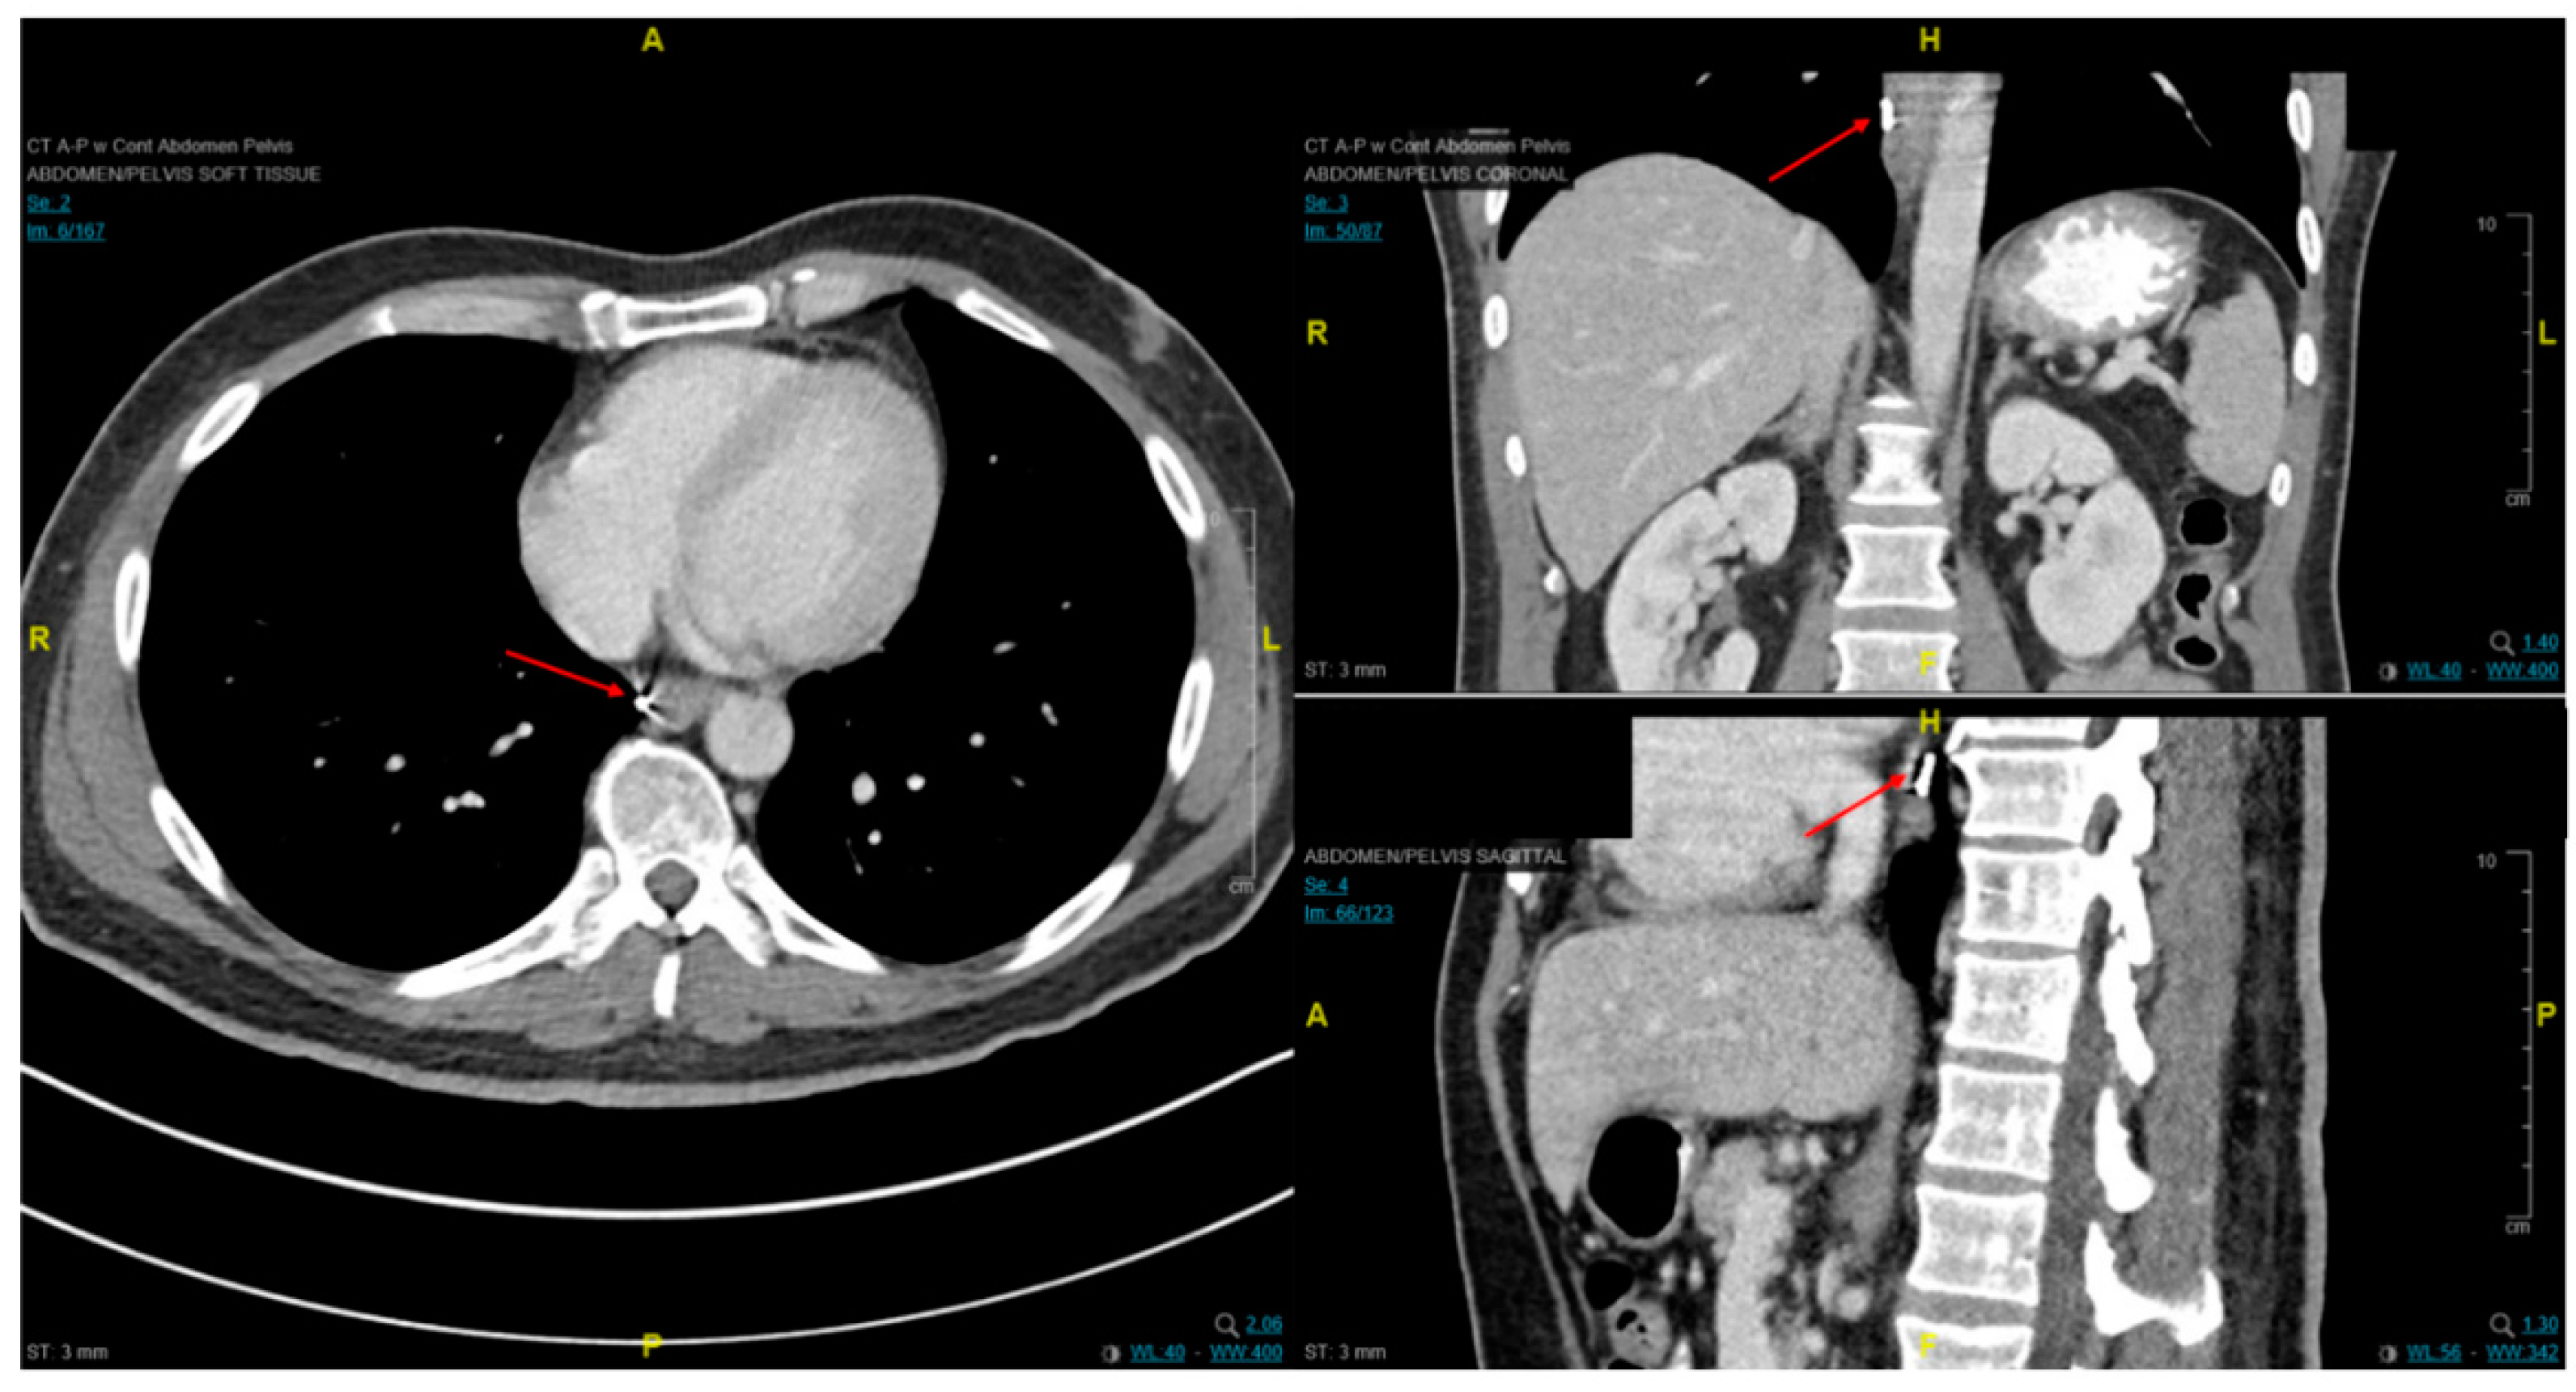

2.2. Distant and Locoregional Staging

4.3. Endoscopic Ultrasound in Staging of Gastric Cancer

4.7. Staging